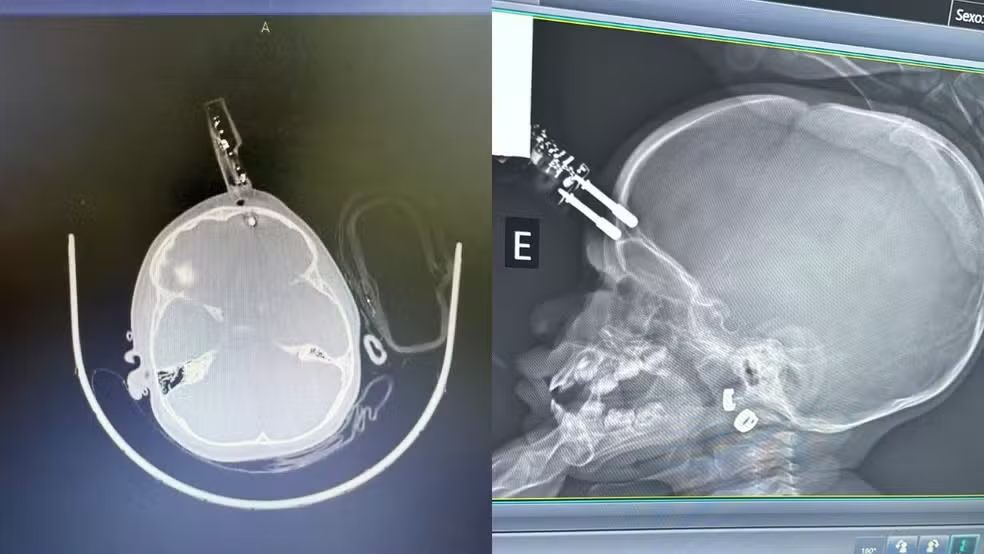

A menina de 1 ano que teve um carregador de celular cravado na testa após cair da cama, em Divinópolis, recebeu alta hospitalar e já está com a família. A informação foi divulgada pelo G1. Apesar da recuperação inicial, a criança deverá passar por acompanhamento neurológico contínuo.

O atendimento foi conduzido pelo neurocirurgião Bruno Castro, responsável pelo caso. De acordo com o médico, a boa evolução inicial está relacionada à capacidade de recuperação do cérebro infantil.

Segundo o especialista, mesmo com a alta hospitalar, o acompanhamento ao longo do tempo é necessário. Lesões cerebrais podem gerar cicatrizes no cérebro, conhecidas tecnicamente como gliose, que podem desencadear crises convulsivas e epilepsia no futuro.